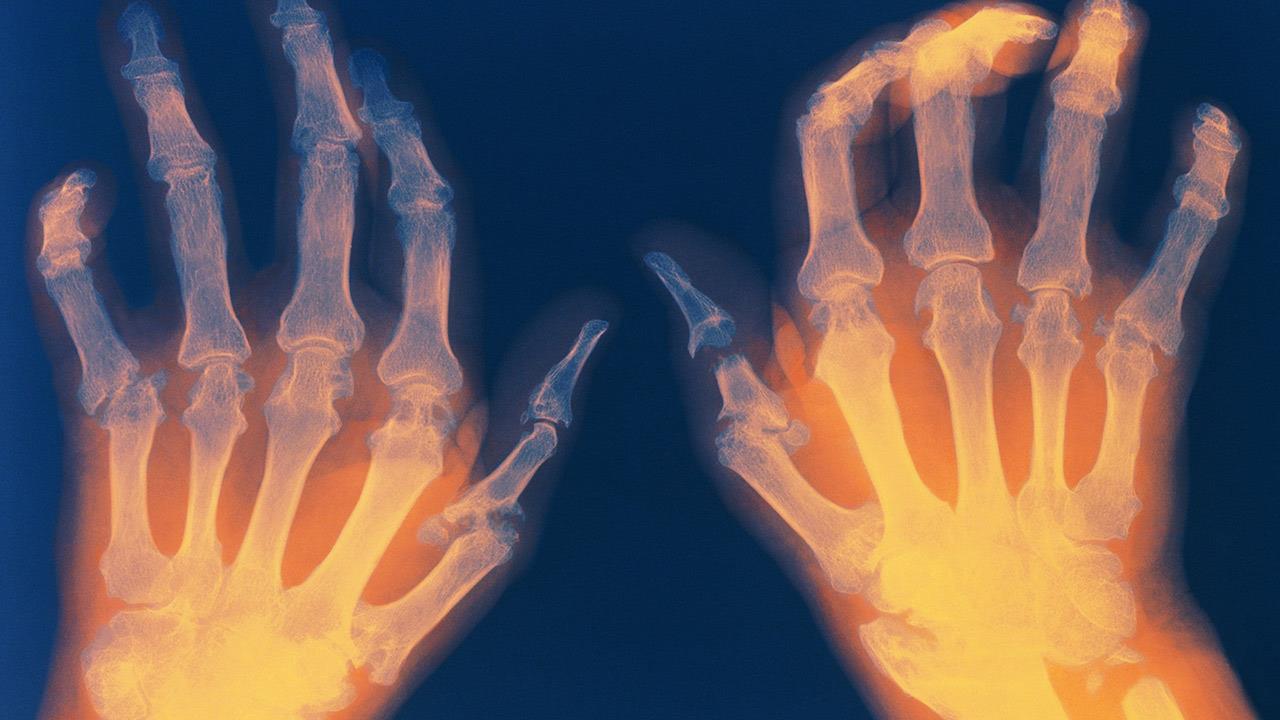

Ένα από τα μεγαλύτερα εμπόδια στη ζωή με Ρευματοειδή Αρθρίτιδα (ΡΑ) είναι η διαχείριση των εξάρσεων – περιόδων όπου τα συμπτώματα επιδεινώνονται απότομα. Αυτές οι εξάρσεις είναι απρόβλεπτες και επηρεάζουν σημαντικά την καθημερινότητα, όπως επισημαίνεται από την Ελληνική Εταιρεία Αντιρευματικού Αγώνα.

• Έντονος πόνος στις αρθρώσεις: Οι αρθρώσεις γίνονται ιδιαίτερα επώδυνες, δυσχεραίνοντας την κίνηση.

• Οίδημα και δυσκαμψία: Η φλεγμονή προκαλεί πρήξιμο και δυσκαμψία, περιορίζοντας την κινητικότητα.

• Μειωμένο εύρος κίνησης: Οι δύσκαμπτες αρθρώσεις περιορίζουν την εκτέλεση βασικών κινήσεων.